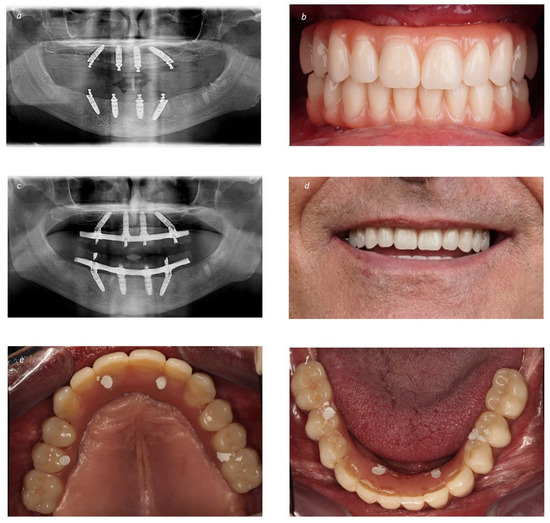

Figure 3.

Prosthetic restoration of the bimaxillary full-arch rehabilitation: (a) Post-operative orthopantomography immediately after surgery; (b) Intraoral frontal photograph with the immediate provisional prostheses; (c) Final orthopantomography at 2 years of follow-up with the definitive prostheses (Maló Clinic Acrylic Bridge—titanium infrastructure, acrylic artificial gingiva and acrylic crowns); (d) Patient smiling with the definitive prostheses in place at 2 years of follow-up; (e) Intraoral occlusal view of the maxillary definitive prostheses at 2 years of follow-up; (f) Intraoral occlusal view of the mandibular definitive prostheses at 2 years of follow-up.